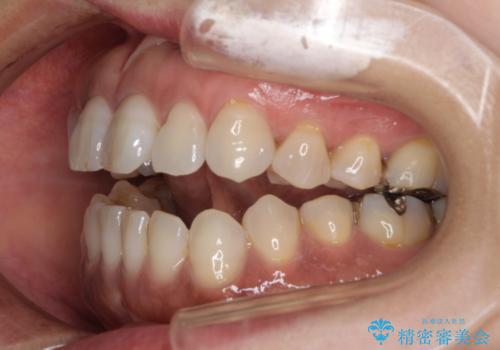

極端な上下前歯の開咬を改善 オープンバイトのインビザライン矯正

- 上下前歯の隙間を気にして来院された患者様です。

開咬の治療は、前歯を閉じるように動かすとともに、上下臼歯を圧下(骨内にめり込ませる)させることで進めて行きます。

インビザラインは臼歯の圧下を効果的に行えるため、インビザラインを用いて矯正治療を行うこととしました。

また、下顎大臼歯に根管治療が必要な歯があるため、矯正治療と並行して治療を行い、矯正後に補綴治療することとしました。

治療前に、いくらインビザライン矯正がオープンバイトを得意としているとは言え、さすがに限界があるだろうと思っておりましたが、前歯でレタスが噛めるまで改善することができました。